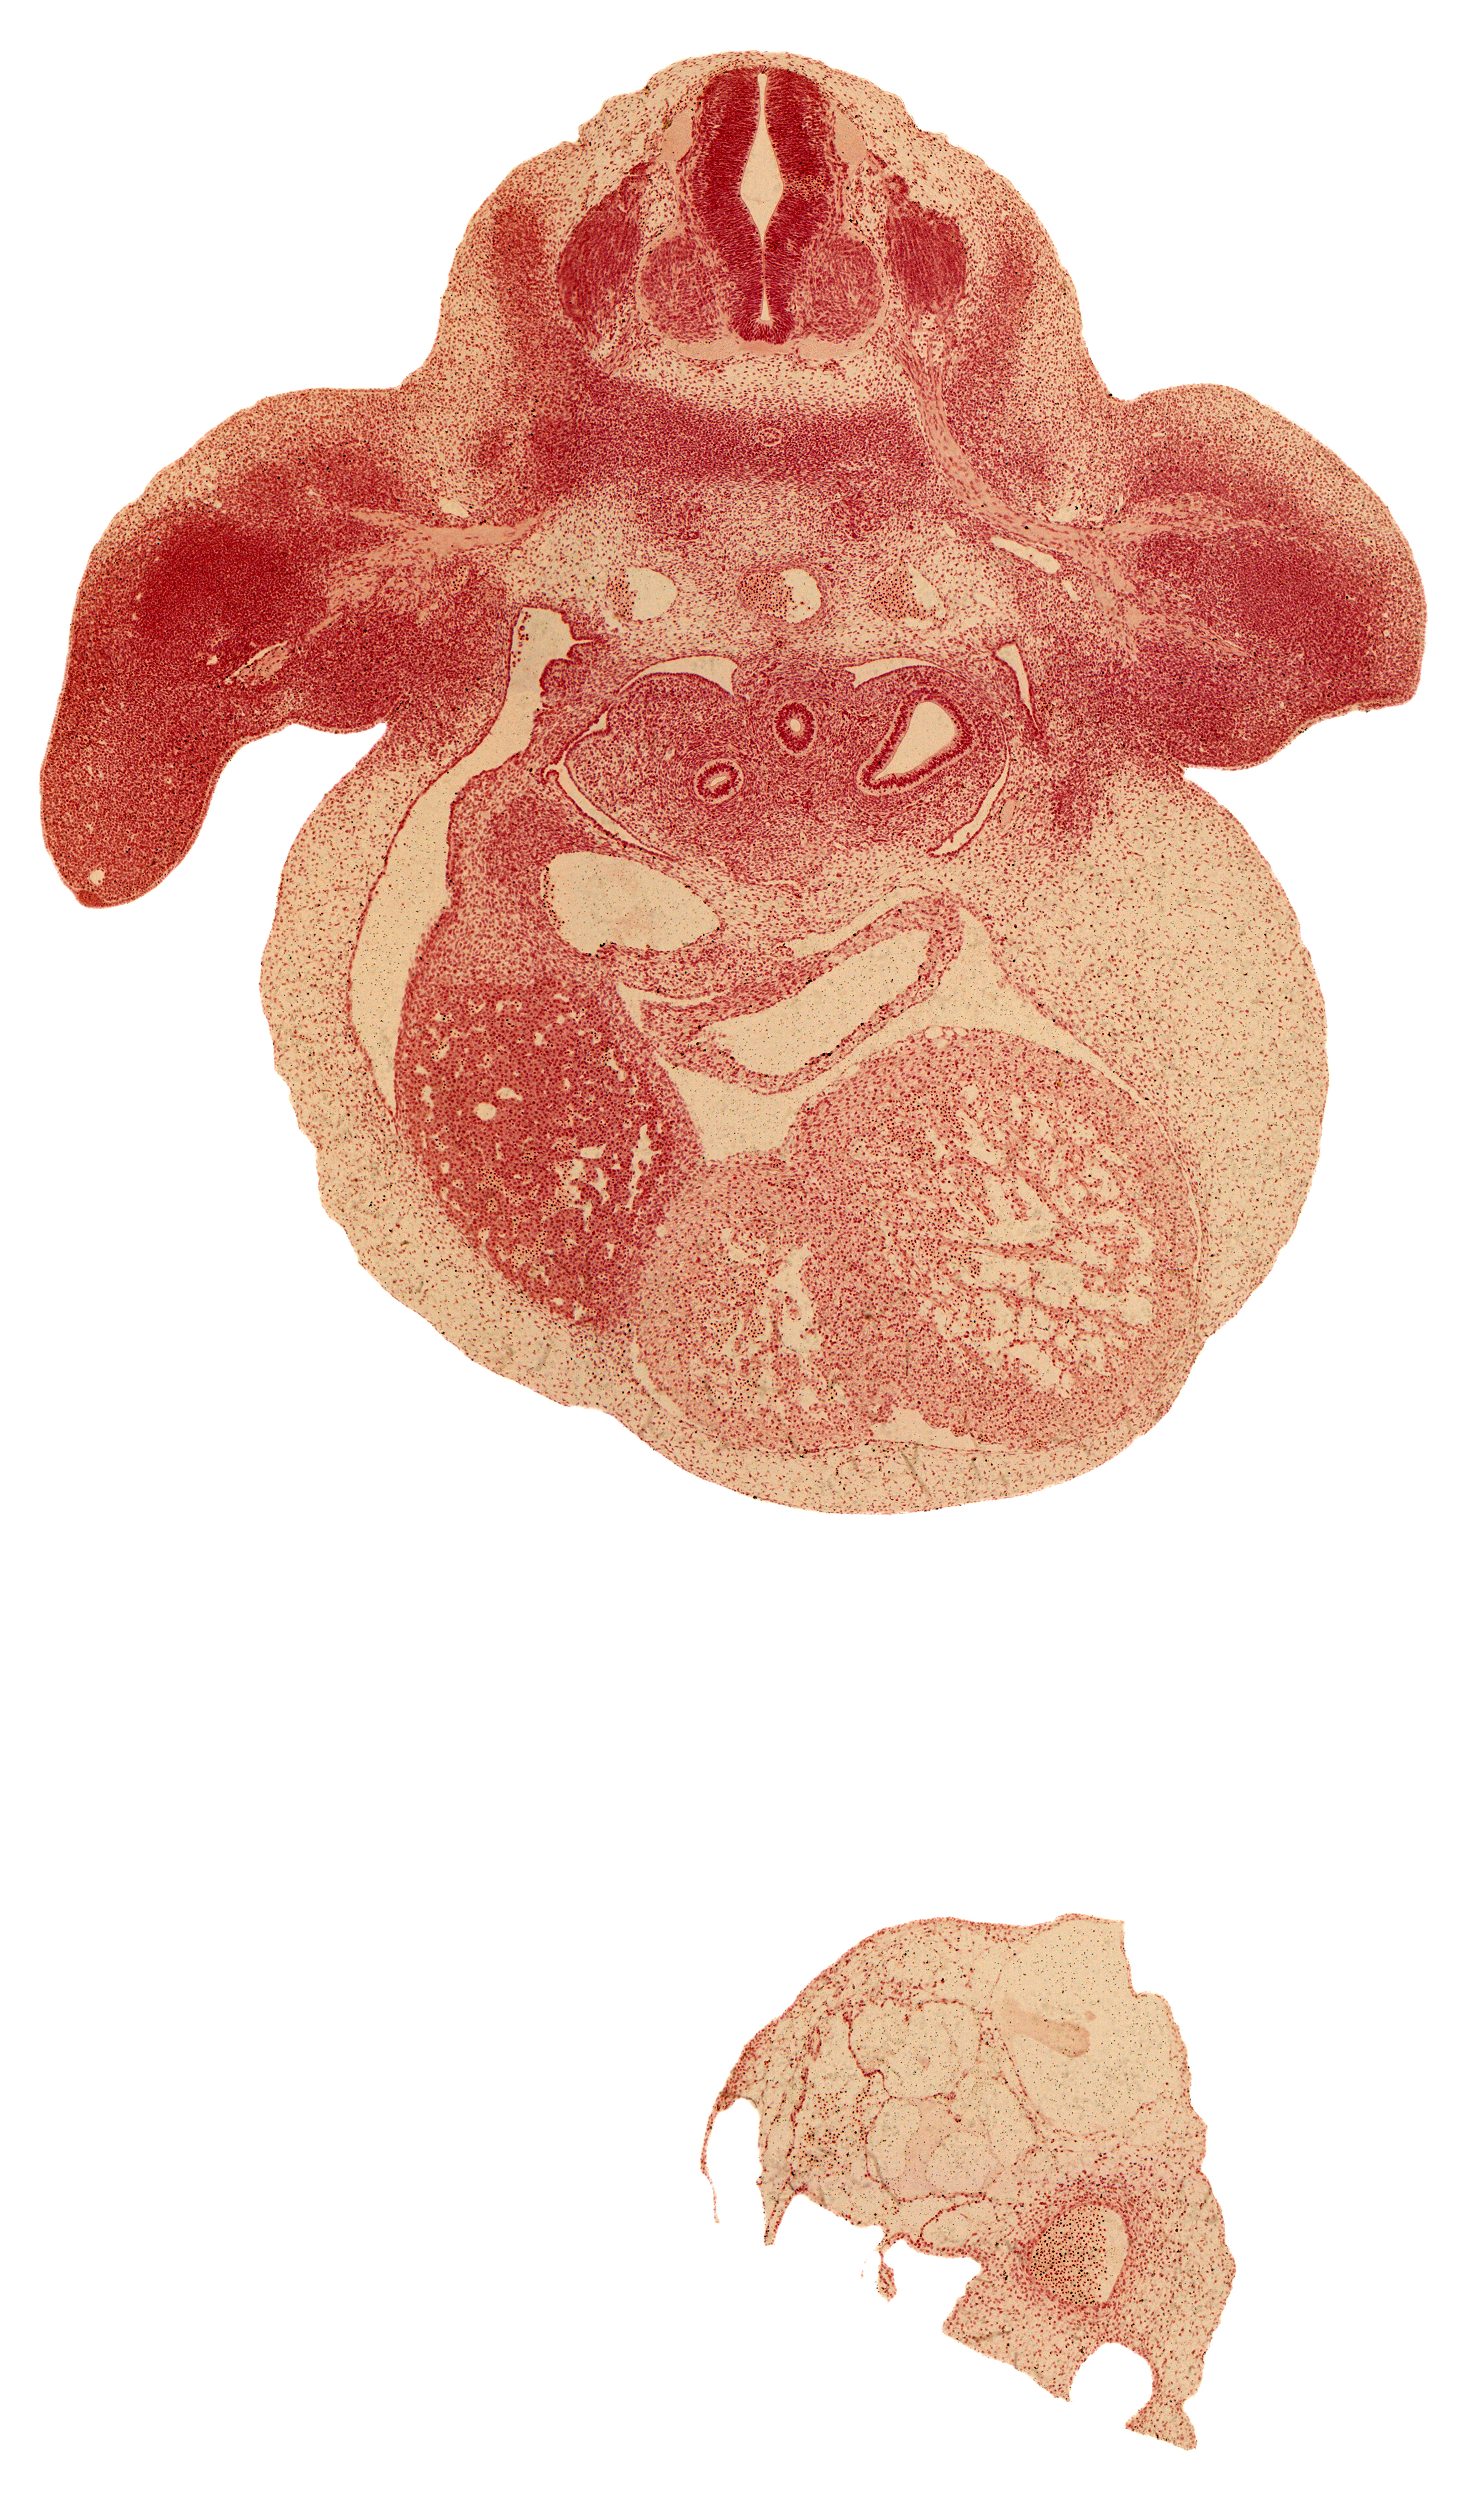

Carnegie Embryo #6517 | Location: 24-02-01

Keywords: C-7 spinal ganglion, C-7 ventral primary ramus, alar plate(s), aorta, basal plate, brachial artery, cardiac prominence, dorsal meso-esophagus, edge of peritoneal cavity, esophagus, left horn of sinus venosus, liver, marginal vein, pericardial cavity, primary bronchus, septum transversum, sinus venosus, skeletal blastema of humerus, sulcus limitans, upper secondary bronchus bud

Source: The Virtual Human Embryo.